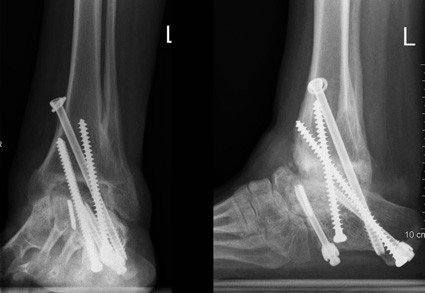

Anfang 2007 wurde die Operation an unserer Klinik durchgeführt.

Intraoperativ zeigte sich, dass die Prothesenkomponente des Sprungbeines und der Anteil des Schienenbeines beide gelockert waren. Der unter der Sprungbeinprothese liegende Knochen zeigte eine ausgeprägte Metallose (=Metallabrieb), die wahrscheinlich durch Schrauben zustande kam, die in der vorgängigen Operation zur Versteifung des unteren Sprunggelenkes verwendet wurden. Der Knochen stellte sich avital und nekrotisch dar. Der nekrotische Knochen muss abgetragen werden bis gesunder, gut durchbluteter Knochen erscheint. Zur Defektfüllung nach Entfernung der Prothesenkomponenten wird der Patientin Knochen aus dem Beckenkamm entnommen und in die Löcher eingelegt. Ergänzend muss Knochenfremdmaterial aus der Knochenbank verwendet werden, um die Defekte ausreichend füllen zu können.

Postoperativ erhielt die Patientin einen Unterschenkelgips für insgesamt drei Monate, eine CT-Untersuchung wurde drei Monate postoperativ geplant, um genau beurteilen zu können, ob der Knochen zusammenwächst.

Die Schichtaufnahmen drei Monate nach der Operation zeigten einen vollständigen Durchbau des Knochens, so dass die Patientin die Belastung auf den Fuss steigern durfte. Zum Schutz trug sie zunächst einen Spezialstiefel für einen weiteren Monat, hiernach wurden Schuhe mit Abrollkomponente angefertigt. Acht Monate nach der Re-Arthrodese stellt sich die Patientin zur regulären Kontrolluntersuchung in unserer Sprechstunde vor.